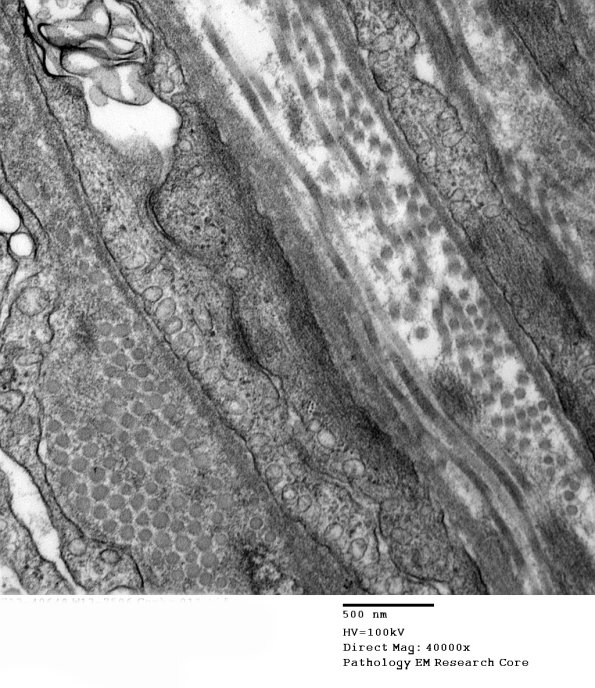

The perineurium shows prominent micropinocytotic vesicles.